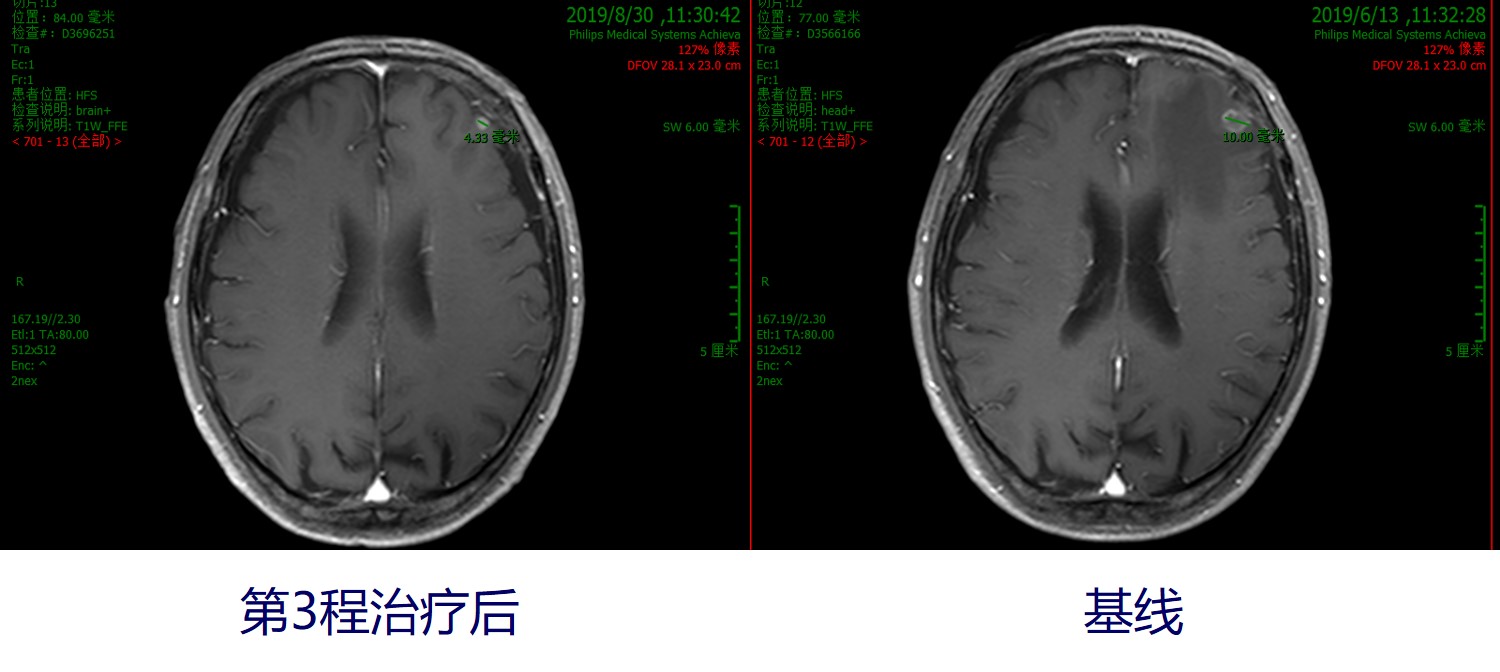

分别于2019年7月11日、2019年8月9日接受第2和第3程减量治疗,具体方案为:信迪利单抗(达伯舒)200mgd1+紫杉醇135mg/m2 d1+DDP 20mg/m2 d1-3(q21d)。治疗后副反应:化疗后不适,体重稳定,血象无异常。2019年8月31日行胸部CT检查示:右肺上叶占位(4.3cm*3.8cm)伴右肺上叶支气管截断、右肺上叶阻塞性改变,纵隔淋巴结肿大:较前(2019年7月9日)右肺上叶渗出实变有所吸收,右肺下叶斑片渗出有所吸收。头颅MRI增强:左侧额叶转移瘤(4mm),较2019年6月13日明显缩小,病灶周围水肿不明显。综合评估患者治疗后的疗效情况,外周血肿瘤标志物下降,见下图1。疗效评估显示:第1次免疫联合化疗后,疗效评价为SD;第3次免疫联合化疗后,疗效评价为PR。